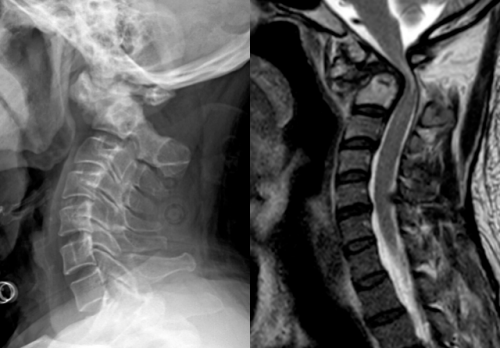

图片

患者术前部分影像